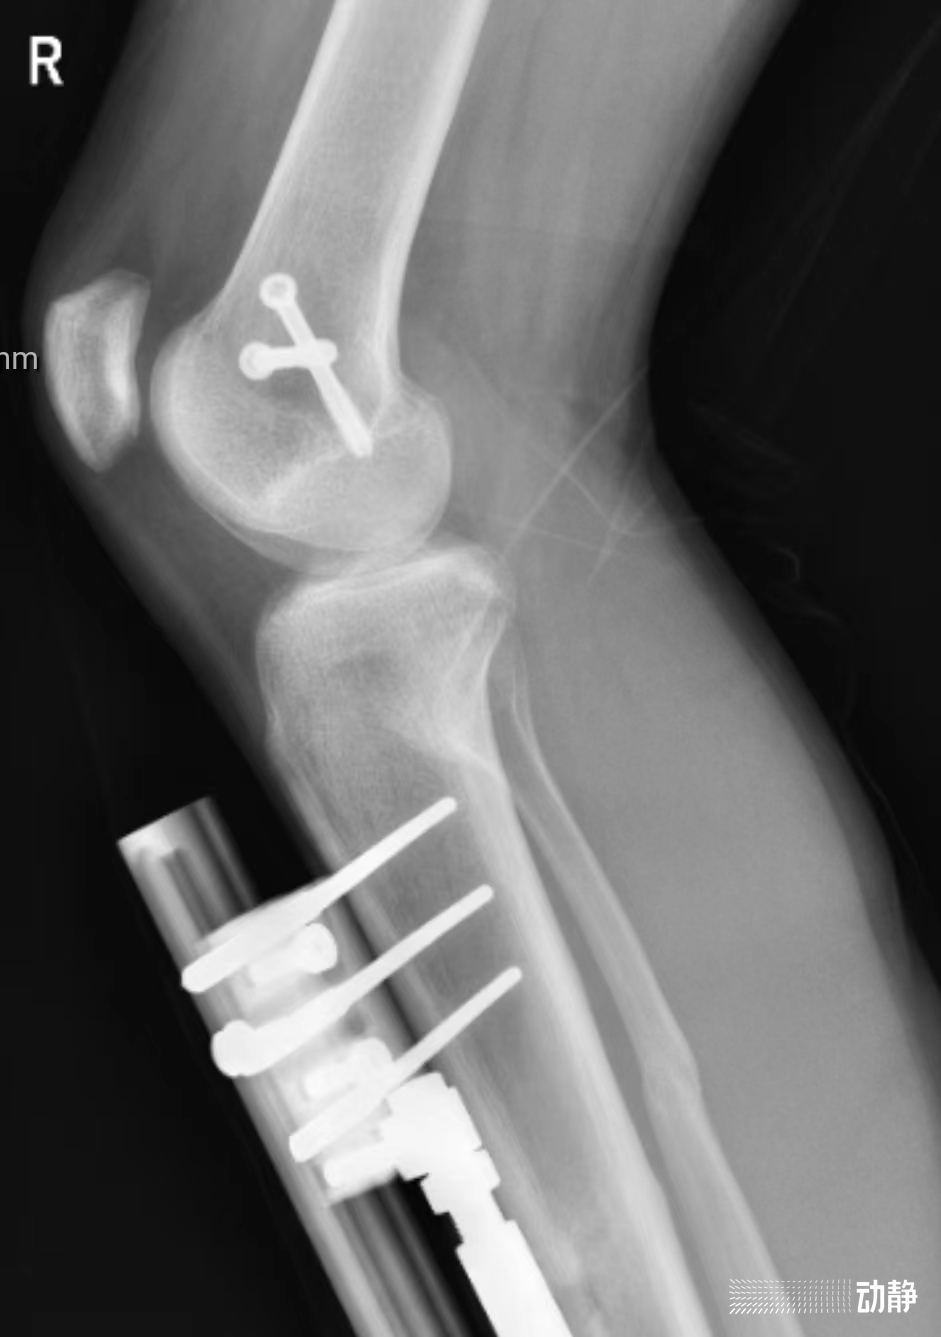

据了解,患者因车祸伤致右下肢畸形、小腿出血,不能站立,在贵阳市第四人民医院显微创伤外科治疗。医院结合病史、查体、X线及CT,初步诊断为“右股骨外髁骨折、右胫骨开放性骨折、右腓骨骨折。

按照传统的治疗方法,像这样的下肢多处骨折需要切开复位内固定,手术时间较长,骨折部位容易在发生粘连,对膝关节活动产生不良影响。为避免这些并发症,显微创伤骨科经过详细的讨论,决定利用胫骨外架固定钉为骨科机器人手术实施创造条件。

经过严密的诊疗和反复论证,创伤治疗团队决定采用骨科机器人进行手术,不仅切口小,而且一次性多次置钉,节省时间,减少创伤,可以让患者得到最佳的治疗效果。